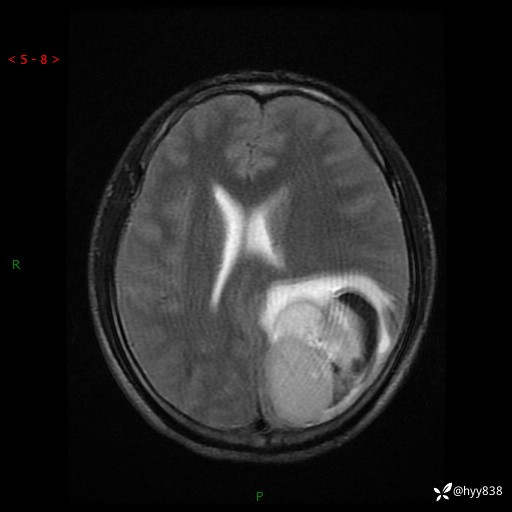

病例年轻小伙,头痛伴呕吐半年,渐进性加重1月。疑难病例,第一次见--结果公布~

性别:男

年龄:21岁

简要病史:头痛伴呕吐半年,渐进性加重1月

颅脑MRI平扫+增强